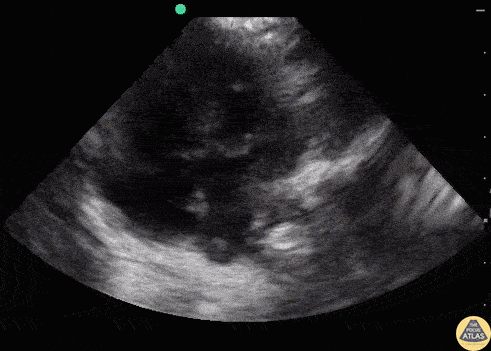

Other Cardiac Pathology - AV Canal Defect

3 month old recent immigrant to the United States with Trisomy 21, presenting with nasal congestion, cough, respiratory distress, with mild abdominal breathing, presumably with bronchiolitis. POCUS was performed to assess the lungs and heart. POCUS revealed a complete AV canal defect which is often seen in Trisomy 21. The interventricular septum has a free end with a common AV valve present and a free end of the ostium primum with ASD. Dr. Sathya Subramaniam - Kings County/SUNY Downstate - Pediatric EM Fellow